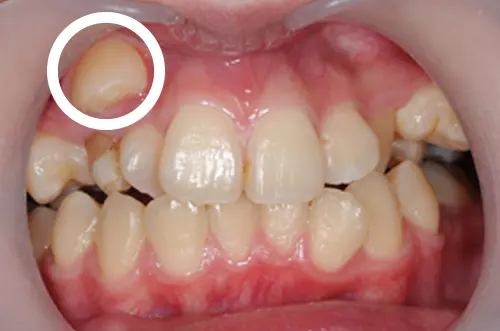

難症例の八重歯のイメージ

一方で、マウスピース矯正だけでは治療が難しいケースも存在します(※2)。例えば、八重歯の原因が歯の並び方だけでなく、顎の骨格そのもののズレに起因している場合や、八重歯が極端に高い位置に生えていて歯根の移動距離が非常に長い場合です。

このような難症例では、歯を大きく平行移動させる力が強いワイヤー矯正の方が適していることや、外科手術を併用する必要が出てくることもあります。無理にマウスピースだけで治そうとすると、治療期間が過度に長引いたり、満足のいく仕上がりにならなかったりするリスクがあります。より適した治療法を検討することが重要です。